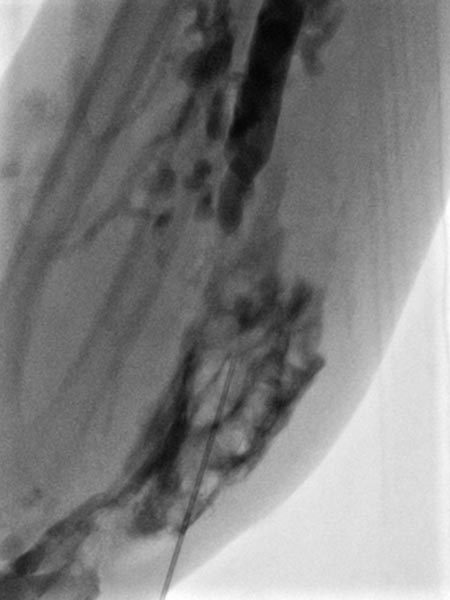

Auch weiter proximal am Unterarm wird schrittweise die gesamte venöse Malformation in der Tiefe der Flexorenmuskulatur ausgeschäumt.

Der Eingriff wird am Unterarm und am Handrücken noch insgesamt 2 mal wiederholt. Am Unterarm gutes klinisches Ergebnis ohne persistierende Schmerzen. Am Handrücken bleiben jedoch klinisch Schmerzen weiter bestehen, auch die Schwellung wird hier (im Gegensatz zum Unterarm) nicht kleiner. Daher wird hier eine lokale Teilresektion der venösen Malformation angeschlossen mit gutem klinischem Ergebnis.